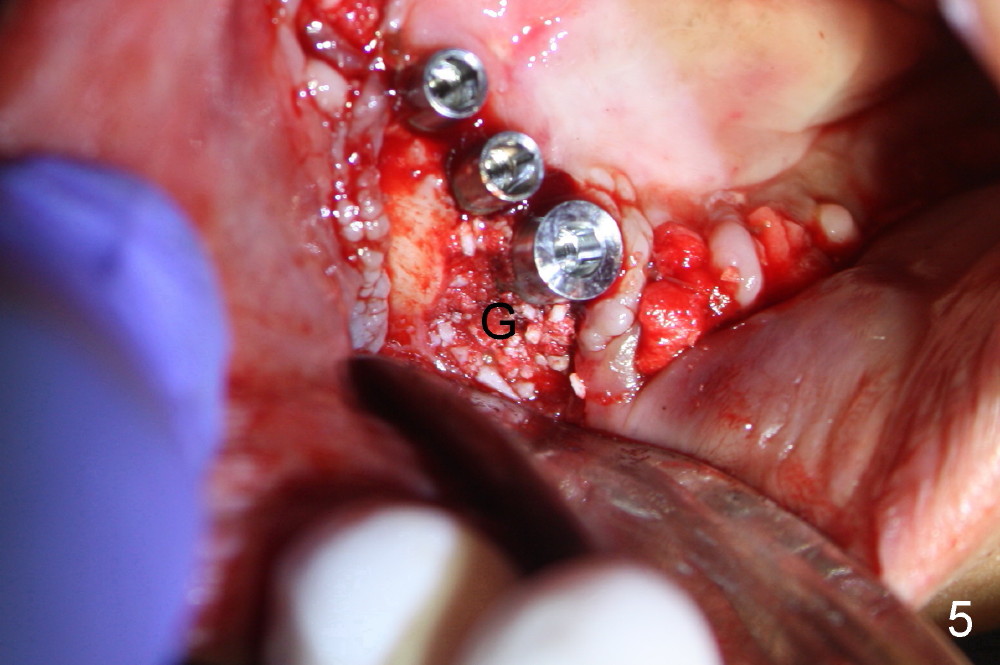

Treatment plan of the 1st surgery consists of extraction of #20 and 21/immediate implants (Fig.1 x), and placement of 4 implants between #22 and 27. Osteotomy at the extraction sites without incision (close surgery) turns out to be difficult; it appears to encroach the inferior alveolar nerve and mental loop. The sockets are subsequently bone grafted (Fig.2 *: mixture of autogenous bone and allograft). Incision is the made in the incisor edentulous region for placement of 3.5x17 mm implants (Fig.3 I).

Osteotomy is initiated through the gingiva of the healing sockets at the sites of #22 and 27 (Fig.1) with difficulty (close surgery). The incisor crest incision is extended distal to the canine areas; an accessory oblique incision is supplemented to facilitate implantation (#22: 5x14 mm; #27: 4.5x17 mm) and expose the buccal defects (Fig.3,4, open surgery). The defects are grafted (Fig.5) and covered by collagen membrane (Fig.6). The incisions are closed and abutments are placed for immediate provisional (Fig.7).